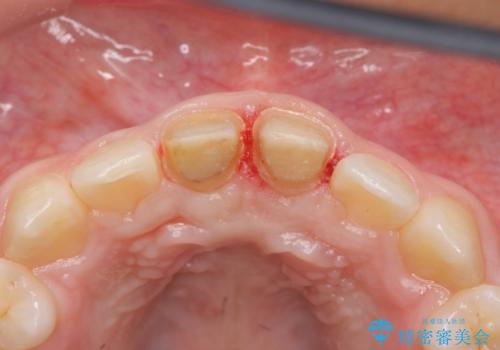

左上の前歯は神経が死んでおり治療が必要な状態でした。また、右上の前歯も根の先に感染がありましたので治療を行いました。

また、プラスチックでつぎはぎになっていたため、虫歯を取りしっかりとしたクラウン(被せもの)としました。